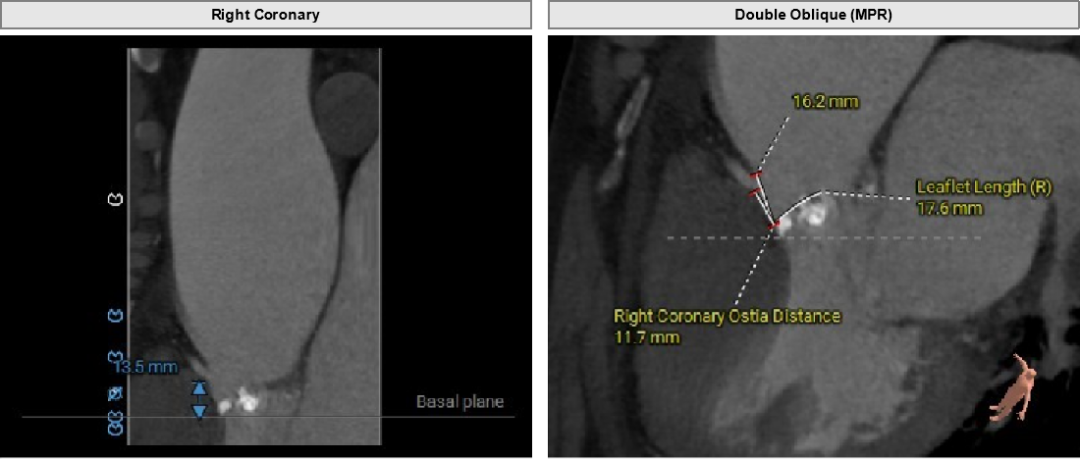

左冠高度17.9mm,右冠高度13.5mm。

瓣口对应瓣叶稍冗长,术中须注意冠脉风险。

主动脉弓角度与宽度可,心脏水平夹角68°,横位心。